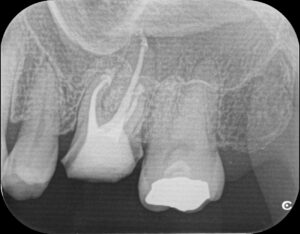

最終洗浄と根管充填、レジンコア(土台)

三か月後に経過のレントゲンを撮影し、最終補綴物を作製するか治りが悪い場合は外科処置(歯根端切除術)の案内になります。